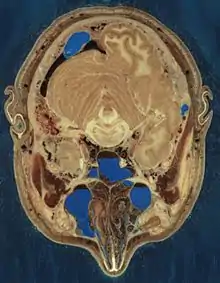

Cryosection through the head of a human male

The male cadaver was encased and frozen in a gelatin and water mixture in order to stabilize the specimen for cutting. The specimen was then "cut" in the axial plane at 1-millimeter intervals. Each of the resulting 1,871 "slices" was photographed in both analog and digital, yielding 15 gigabytes of data. In 2000, the photos were rescanned at a higher resolution, yielding more than 65 gigabytes. The female cadaver was cut into slices at 0.33-millimeter intervals, resulting in some 40 gigabytes of data.

The data are supplemented by axial sections of the whole body obtained by computed tomography, axial sections of the head and neck obtained by magnetic resonance imaging (MRI), and coronal sections of the rest of the body also obtained by MRI.

Freezing caused the brain of the man to be slightly swollen, and his middle ear ossicles were lost during preparation of the slices. Nerves are hard to make out since they have almost the same color as fat, but many have nevertheless been identified. Small blood vessels were collapsed by the freezing process. Tendons are difficult to cut cleanly, and they occasionally smear across the slice surfaces.